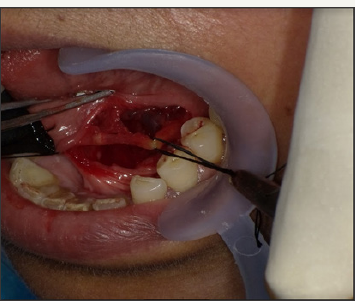

After appropriate preparation and draping, a mouth prop was inserted on ipsilateral side and tongue retracted with a suture. An incision was given with an imaginary line running across the duct with a lateral inclination anteriorly and medial inclination posteriorly. This is done to oppose the path of lingual nerve which is exactly opposite to the incision line, i.e. lingual nerve crosses the duct from below, lateral to medial, in premolar-molar region. A combination of blunt and sharp dissection was used to expose the anterior duct. The point of lingual nerve traversing the duct was identified and lingual nerve protected. Duct was further dissected posteriorly. However, the ductal stone could not be visualised. On applying extraoral pressure to push the deeper part of duct intraorally, the sialolith was seen. Duct posterior to the obstruction was edematous. As an incision was given in the duct over the stone, a spurt of pus threw the stone out (Figure 10 & 11). Gland was further milked and resulted in expression of more pus. Milking was continued till normal salivary flow was observed. The floor of mouth was sutured with 4-0 resorbable suture. Patient was kept on broad spectrum antibiotics and discharged after 2 days. Recovery was uneventful. However, salivary flow was close to nil for about 3 weeks. Patient has been followed up for around 8 months. Some part of the gland has become fibrosed and salivary flow has increased but still less as compared to opposite side.

Figure 10: Operative picture showing the incised part of the duct.